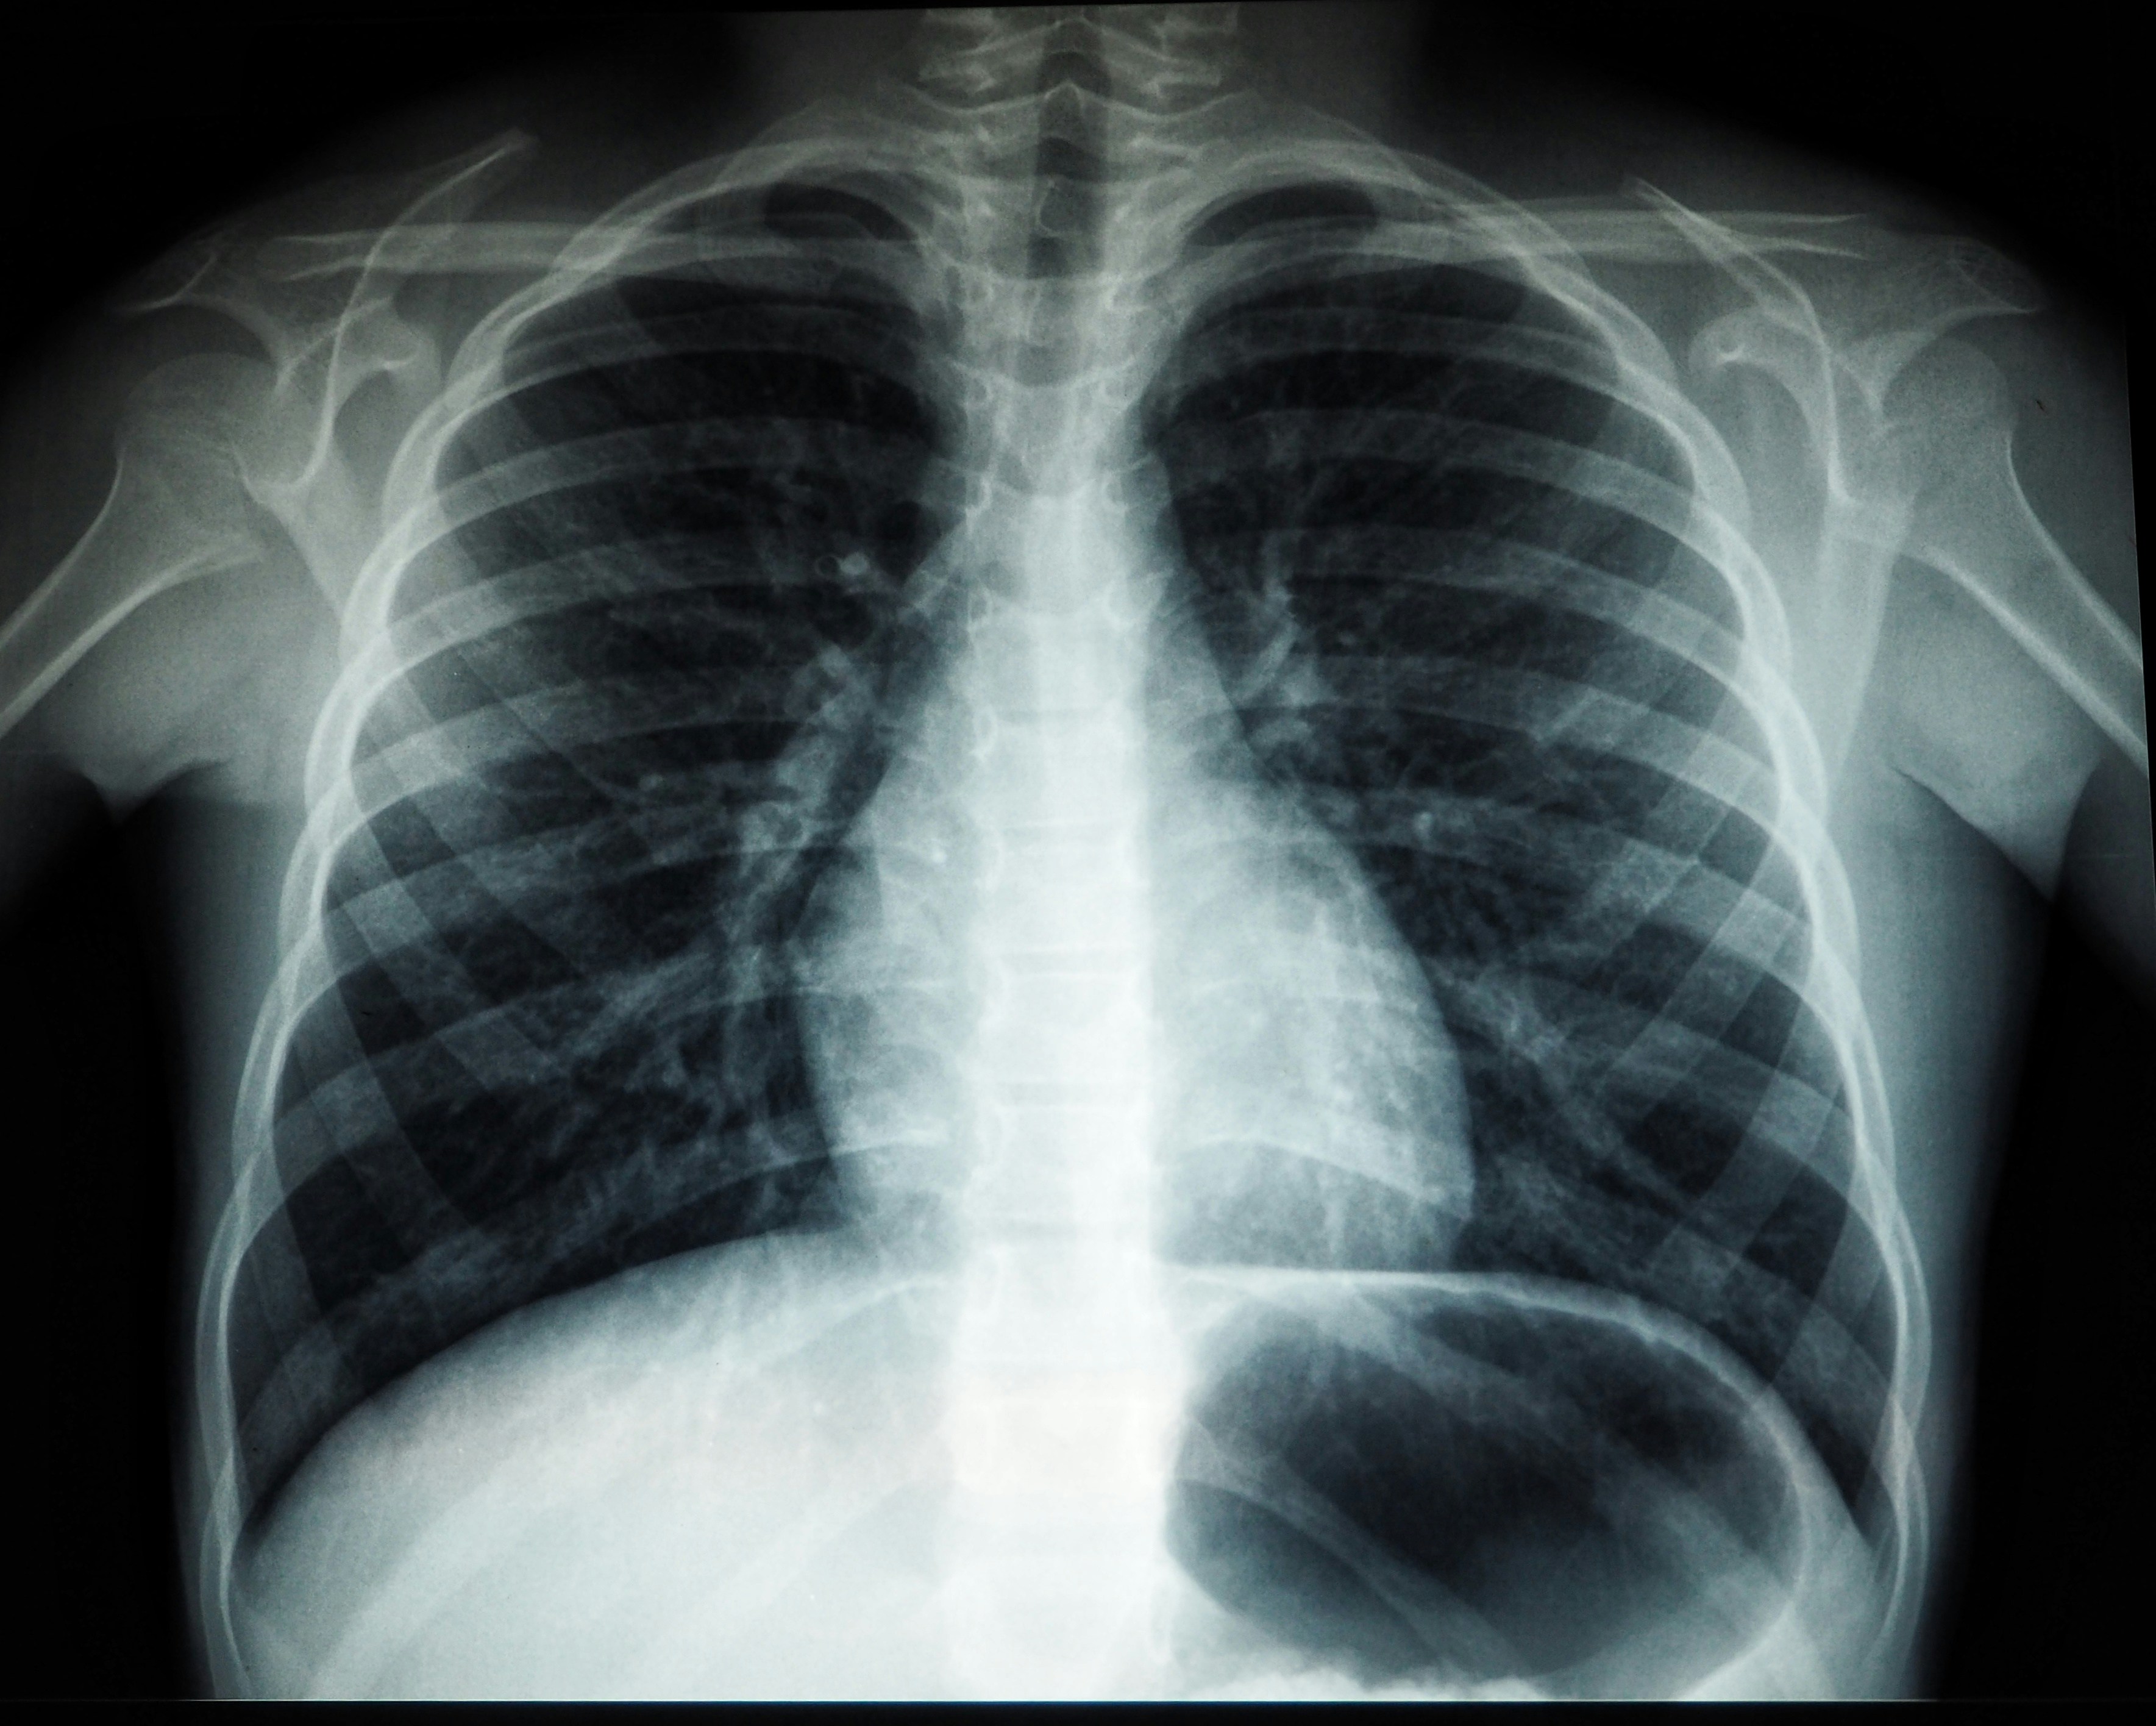

Szczepienia na gruźlicę. Czy Polska powinna z nich zrezygnować?

Gruźlica jest chorobą zakaźną wywołaną przez bakterie – prątki gruźlicy z grupy Mycobacterium tuberculosis complex, a główną drogą zakażenia jest zarażenie od osoby chorej, np. wraz z wydychanym powietrzem. Choroba rozwija się u ok. 5–10 proc. osób zakażonych.